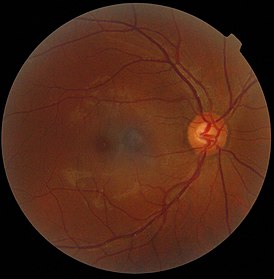

Фотография сетчатки глаза человека

Около центра сетчатки (ближе к носу) на задней её поверхности находится диск зрительного нерва, который проецируется с височной стороны. Из-за отсутствия в этой части фоторецепторов эту зону называют слепое пятно или пятно Мариотта. Диск зрительного нерва выглядит как бледная, округлой формы, зона около 3 мм². Здесь из аксонов ганглионарных нейроцитов сетчатки происходит формирование зрительного нерва. В центральной части диска имеется углубление, через которое проходят сосуды, участвующие в кровоснабжении сетчатки.

Латеральнее диска зрительного нерва, приблизительно в 3 мм, располагается пятно (macula), в центре которого имеется углубление, центральная ямка (fovea), являющееся наиболее чувствительным к свету участком сетчатки и отвечающее за ясное центральное зрение (жёлтое пятно). В этой области сетчатки (fovea) находятся только колбочки. Человек и другие приматы имеют одну центральную ямку в каждом глазу в противоположность некоторым видам птиц, таким как ястребы, у которых их две, а также собакам и кошкам, у которых вместо ямки в центральной части сетчатки обнаруживается полоса, так называемая зрительная полоска. Центральная часть сетчатки представлена ямкой и областью в радиусе 6 мм от неё, далее следует периферическая часть, где по мере движения вперед число палочек и колбочек уменьшается. Заканчивается внутренняя оболочка зубчатым краем, у которого фоточувствительные элементы отсутствуют.

На своём протяжении толщина сетчатки неодинакова и составляет в самой толстой своей части, у края диска зрительного нерва, не более 0,5 мм; минимальная толщина наблюдается в области ямки жёлтого пятна.